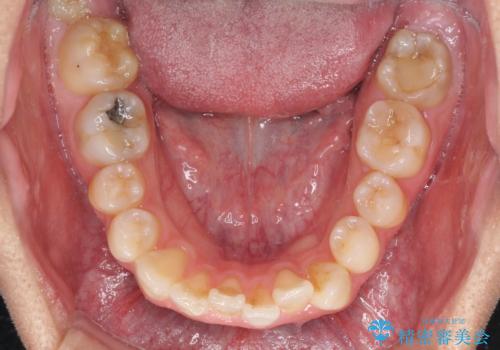

顎が左右にずれた咬み合わせ ハーフリンガルの抜歯矯正

上下の顎骨が左右に大きくずれており、奥歯が交叉咬合となっていたため、ハーフリンガルよりも表側装置をおすすめしましたが、目立たない装置を強く希望されたため、治療期間が長期化することを前提に、ハーフリンガルにて抜歯矯正を行うこととしました。

裏側装置での交叉咬合改善は非常に困難なもので、頻繁に装置の脱落がありました。